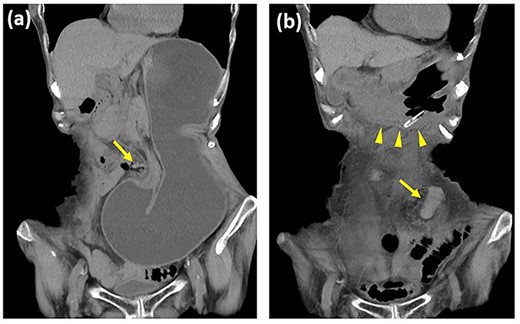

Three months after the surgery, the patient presented with lower abdominal pain and vomiting. Contrast-enhanced computed tomography (CT) showed gastric incarceration through the space between the lifted sigmoid colostomy and the left lateral abdominal wall (Fig. 1a). Because the incarcerated stomach had no evidence of strangulation, conservative therapy with nasogastric tube decompression of the dilated stomach was administered. A CT on the next day showed the reduction of the stomach (Fig. 1b), and oral intake was started. However, the patient again began vomiting on the 7th and 13th days after admission, and a CT on the 13th day revealed recurrence of the gastric hernia.

Contrast-enhanced computed tomography images of the gastric internal hernia. (a) The stomach is incarcerated through the lateral defect of the lifted sigmoid colostomy (arrow). (b) The stomach (arrowhead) is reduced after nasogastric tube decompression.